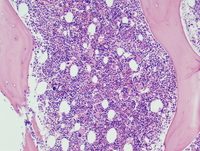

Bone marrow core biopsy

The bone marrow is usually hypercellular. Dysplastic megakaryocytes are frequently seen. CD34 immunohistochemical stain can be helpful in the identification of blasts on the bone marrow core biopsy.